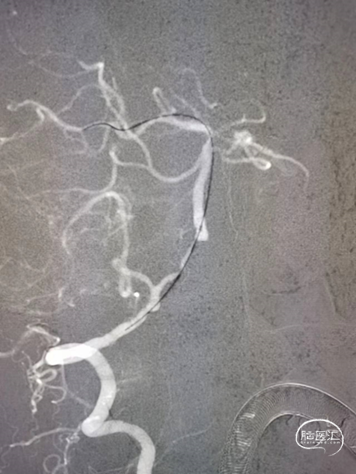

在颅内支撑导管支撑下,将0.014'' 300cm微导丝,通过狭窄节段将其放置在基底动脉中段。将2.0mm*10mm球囊打起预扩狭窄部位,然后更换赛诺神畅 颅内药物洗脱支架NOVA DES® 2.5*10mm延微导丝顺利通过狭窄节段,再次造影见定位准确,缓慢扩张球囊释放支架。

术后影像

术后即刻影像及患者术后情况:

造影见狭窄位置狭窄解除,支架贴壁良好,后循环各分支动脉显影良好。术后次日患者行走不稳情况明显改善,术后1月随访患者行走如常,未再发头晕。